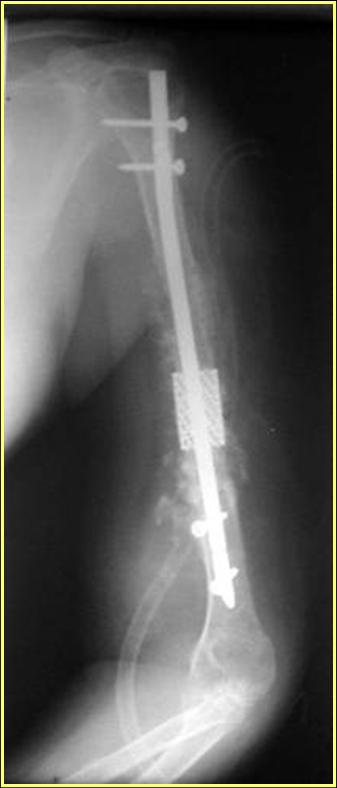

Типичная положительная ситуация для интрамедуллярного остеосинтеза с

использованием опорного металлокаркаса для компенсации дефекта.

Послеоперационное ведение активное или агрессивно-активное. Каркасы

можно заказать в МАТИ.

Рентгеновская версия реконструкции. хронология:

после операции, 2 мес. после операции, через 1 год

Движения в полном объеме восстановлены к 2 мес. после операции. Если надо могу показать мультик. Сейчас уже прошло более 3 лет, больная не

показывается. Успехов ЛАФ.